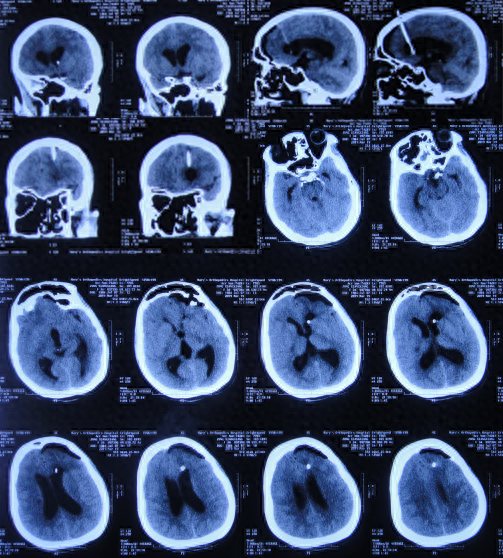

小脑扁桃体下疝减压术后28天即2019年3月14日,仍头痛剧烈,间断发热,转至上级的河南省郑州市某三甲医院。于2019年3月15日,查头颅CT(图-10)后进行了腰大池引流治疗,引流后头痛仍无缓解,引流出脑脊液呈淡黄色,浑浊,考虑颅内感染。

图-10:2019年3月15日头颅CT

给予腰大池引流术后3天,仍发热且头痛,该院医生建议转至北京的李小勇脑脊液科。